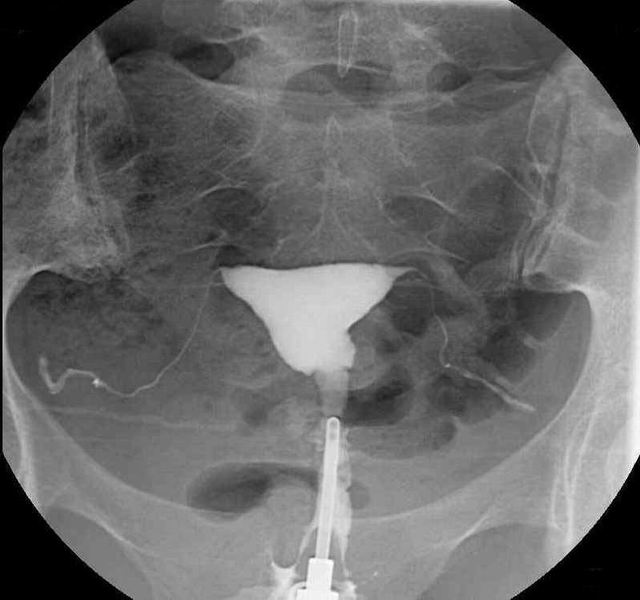

Cystografie